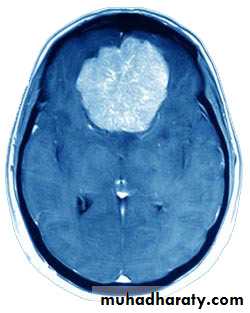

Metastatic Brain TumoursMRI